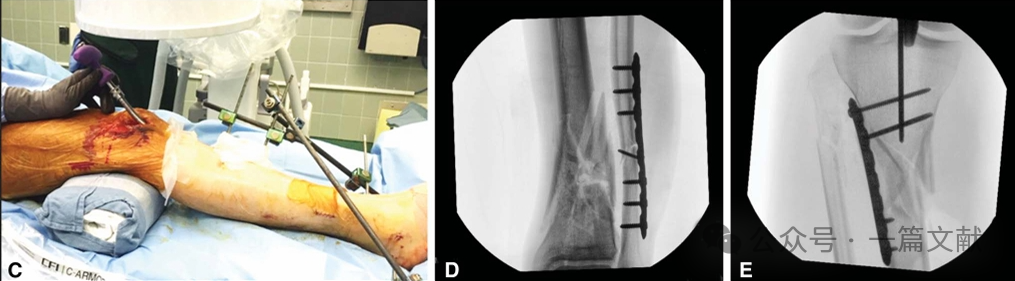

图4,“手指”技术调整导针方向:使用“手指”或空心髓内钉复位杆可以帮助骨折复位或调整导针的轨迹。在本例中,在入口扩髓后使用“手指”装置,以防止球头导丝抵住后侧皮质。其有助于提高髓内钉置入的精确性。

(A) 钳子是非常有用的辅助工具,尤其是在螺旋形或斜形骨折中,可以通过经皮方式实现解剖复位。

(B) 通过手动牵引和锤子或其他工具来维持冠状面对齐,尤其是在严重粉碎性骨折中。也可以在骨折后方放置毛巾垫,特别是在远端三分之一骨折中,以防止成角畸形。

(C) 在助手有限的情况下,可以考虑使用外固定器或股骨撑开器,必须妥善地应用以实现骨折复位的同时,避免干扰髓内钉的置入。

(D) 腓骨钢板固定特别适用于严重胫骨粉碎性骨折伴简单腓骨骨折的情况,以重新建立胫骨的长度、对线和旋转。

(E) 临时胫骨钢板固定可用于复杂骨折或开放性骨折伤口。螺钉可以是单皮质或避开髓内钉路径,以便在髓内钉置入时进行扩髓。在髓内钉交锁后可以移除钢板。